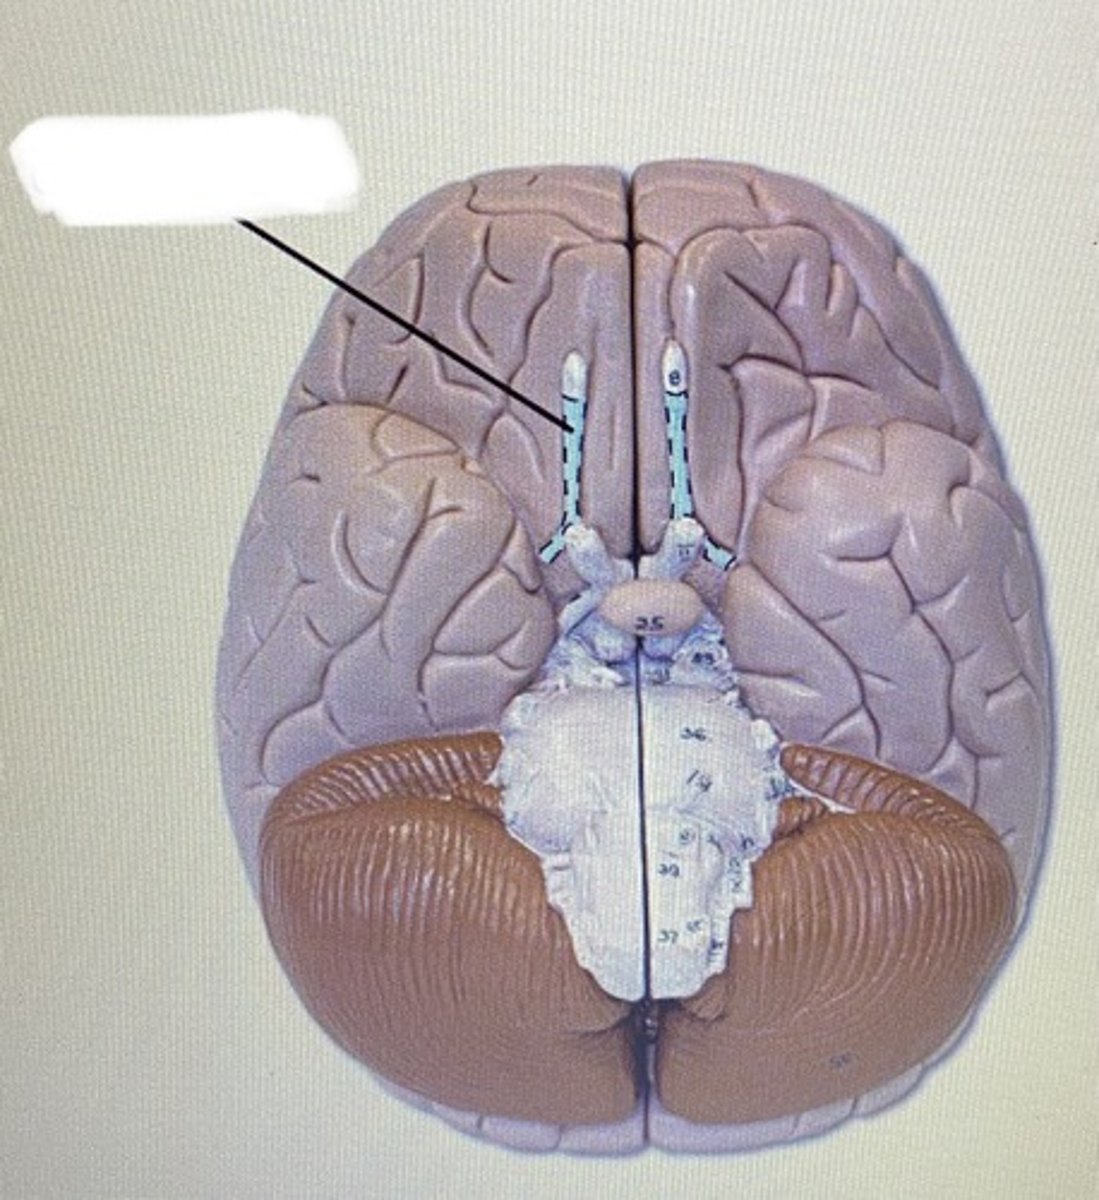

Olfactory Bulb & Tract

-sense of smell

-nerve 1

Optic Nerve & Optic Chiasm

-vision

-nerve 2

Oculomotor Nerve

-controls eye movement

-nerve 3

Pons

-bridge that links medulla oblongata to thalamus

Medulla Oblongata

-houses autonomic centers

Sheep Longitudinal Fissure

Sheep Corpus Callosum

Sheep Third Ventricle

sheep corpus callosum

Sheep optic chiasm

Sheep Pineal Gland

Sheep superior colliculus

Sheep Cerebellum

sheep 4th ventricle

Sheep Central Canal

Sheep Optic Chiasm

Sheep Pons